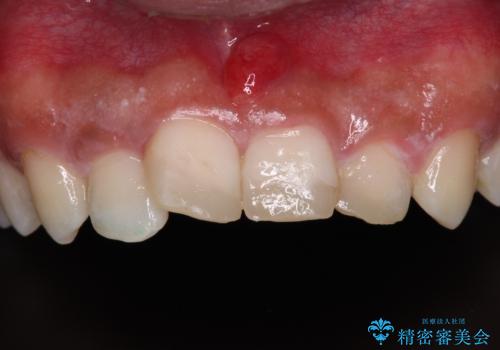

転んでぶつけて抜歯 前歯のオールセラミックブリッジ

- 酒席の後に転倒して前歯を損傷し、応急処置のみを受けてきたとのことで来院された患者様です。

損傷がひどく、前歯4本と広範囲であったため、症状やレントゲン写真、検査結果が一致せず、定期的に経過を見ながら診断していくこととしました。

右側前歯は歯根が短くなり、パンチング状に歯根に透過像が認められたため、予後不良と判断し抜歯することとしました。

当初のレントゲン写真では根尖部に骨透過像が認められた両サイドの2歯は、歯髄の正常な反応が認められたためそのまま保存し、左側前歯は歯髄が失活していたため根管治療を行うこととしました。

抜歯後の欠損部はブリッジにて補綴治療を行うこととしました。

事故直後のレントゲン写真では全ての歯の根尖部に骨透過像が認められましたが、治療後には全ての透過像がなくなっていました。

診断に2-3ヶ月かかりましたが、的確に診断を行うことができました。